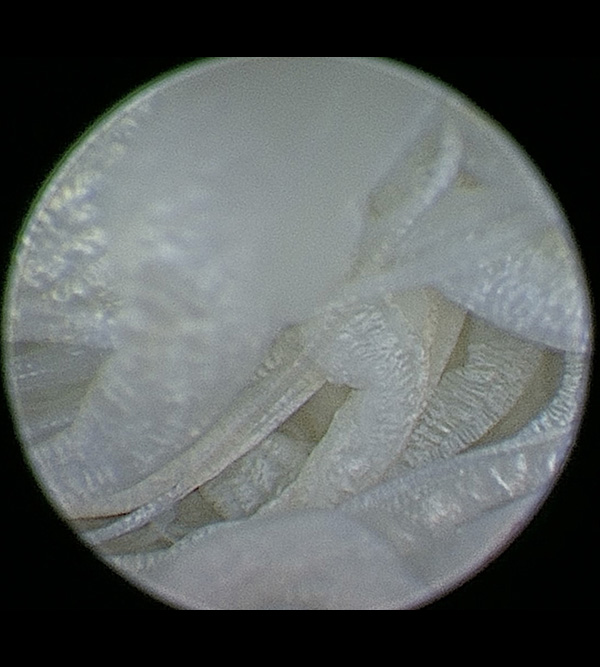

Your dog’s stifles (i.e., knee joints) absorb a lot of impact as they run, jump, and play. To understand cranial cruciate ligament rupture, you must first understand the components of the stifle joint. This stifle is composed of the femur (i.e., thigh bone), tibia (i.e., shin bone), and patella (i.e., kneecap). Four ligaments—the cranial cruciate, caudal cruciate, medial collateral, and lateral collateral ligaments—are primarily responsible for stabilizing the stifle. The medial and lateral menisci act as cushions between the femur and tibia, and help provide congruency and further stabilize the joint.